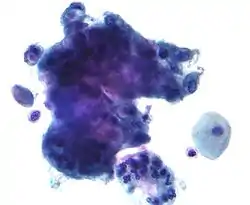

Squamous metaplasia of the cervix, with typical features. Pap stain.

Pap tests commonly examine epithelial abnormalities, such as metaplasia, dysplasia, or borderline changes, all of which may be indicative of CIN. Nuclei will stain dark blue, squamous cells will stain green and keratinised cells will stain pink/ orange. Koilocytes may be observed where there is some dyskaryosis (of epithelium). The nucleus in koilocytes is typically irregular, indicating possible cause for concern; requiring further confirmatory screens and tests.